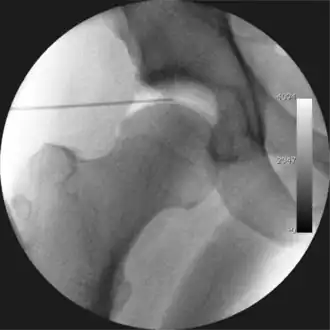

Figure 3. Fluoroscopic picture showing a mild amount of distraction of the hip before insertion of any instruments -

The procedure is performed with the patient asleep (general anaesthetic) or under spinal anaesthesia. There are two widely used methods, one with the patient on their back (supine) and the other on their side (lateral decubitus). Which is used is down to the surgeon's preference. To gain access to the central compartment of the hip joint (between the ball and socket), traction is applied to the affected leg after placing the foot into a special boot. (See fig. 2) There is specifically designed equipment for this, although some surgeons use a 'traction table', initially designed to help in the operative fixation of broken thigh and lower leg bones. The amount of traction (or pull) needed is assessed with the help of fluoroscopy (low-dose portable x-ray). (See fig. 3) It is usually not possible to distract the ball from the socket with traction alone by more than a few millimetres. Once the surgeon is happy that they will be able to gain access to the hip joint (i.e. the ball will distract from the socket by a small amount), the patient is then painted with antiseptic and the surgical drapes applied.